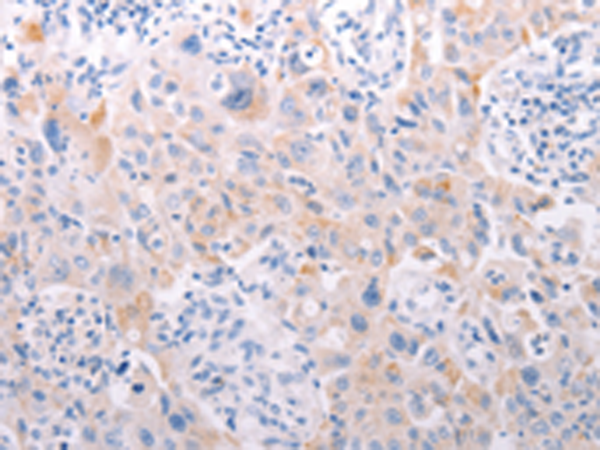

分类: 科研抗体货号: P11172别名:应用: IHC反应种属: Human, Mouse

分类: 科研抗体货号: P11170别名: PAQR2; ACDCR2应用: IHC反应种属: Human, Mouse

分类: 科研抗体货号: P11167别名: DSH; AGS6; G1P1; IFI4; P136; ADAR1; DRADA; DSRAD; IFI-4; K88DSRBP应用: IHC反应种属: Human

分类: 科研抗体货号: P11175别名:应用: IHC反应种属: Human

分类: 科研抗体货号: P11187别名: ANKRA应用: IHC反应种属: Human, Mouse

分类: 科研抗体货号: P11166别名: ADAM-TS6; ADAMTS-6; ADAM-TS 6应用: IHC反应种属: Human

分类: 科研抗体货号: P11174别名: AYTL3; AGPAT7; LPEAT2; LPAAT-eta应用: WB,IHC反应种属: Human, Mouse

分类: 科研抗体货号: P11186别名:应用: IHC反应种属: Human